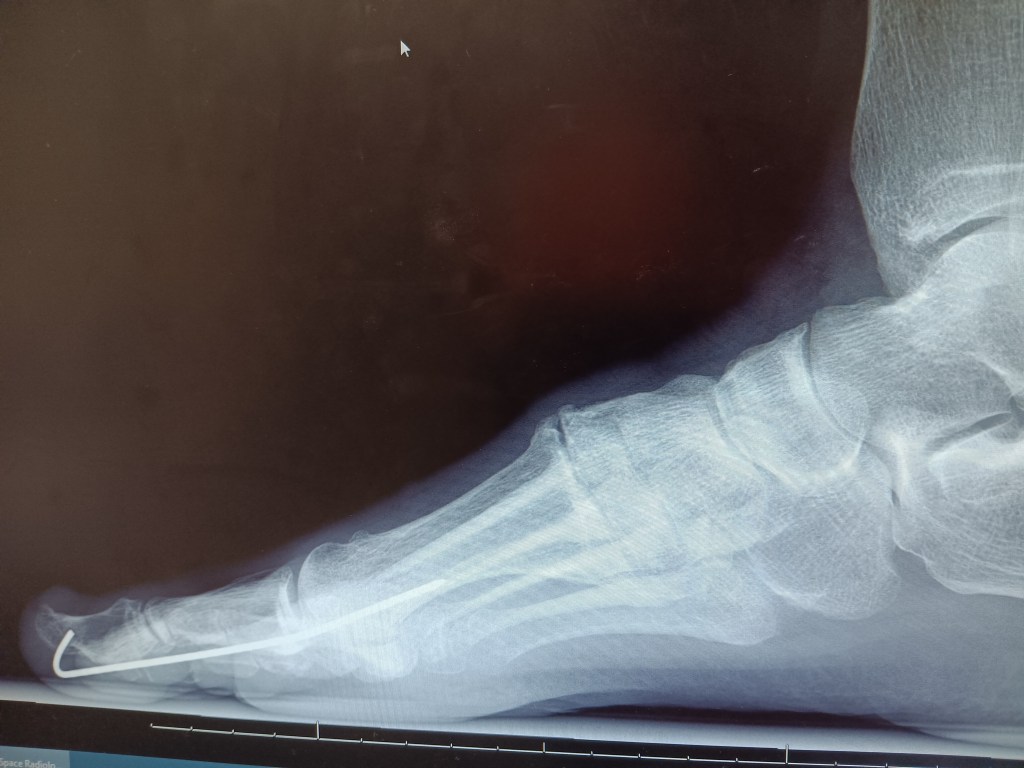

‘Hammer toe’ is a joint dislocation that can only be corrected, in its ‘frozen’ state, by surgery of the affected toes, ligaments and muscles. The surgeon removes bone so the toes can lie flat again and pins are inserted to make them heal that way. The pins will be removed later.’

On Halloween my sister took me in for x-rays and pin removal- thanks sis! Surprisingly, the doctor uses a common pair of slip-joint pliers to quickly twist and jerk out the pin with virtually no pain. That was a happy day since it’s deeply weird to clump around with a steel pin in the toe.